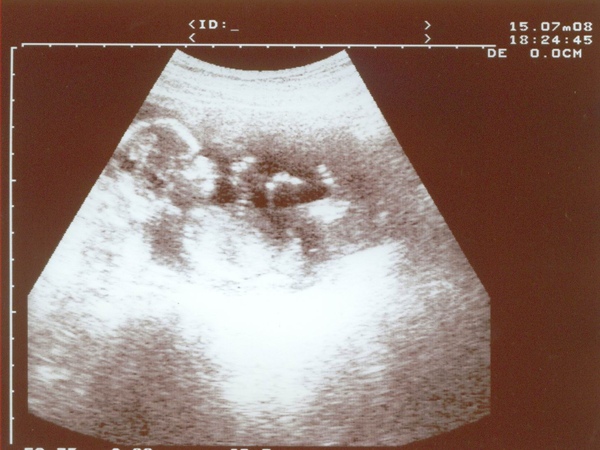

本週四早上去照超音波 完整的將周小熊照過1次

確認了她健健康康 而萬眾期待的答案揭曉 登登

周小熊是女生,也就是,她是小長頸鹿

奉上漂亮小長頸鹿照片1張